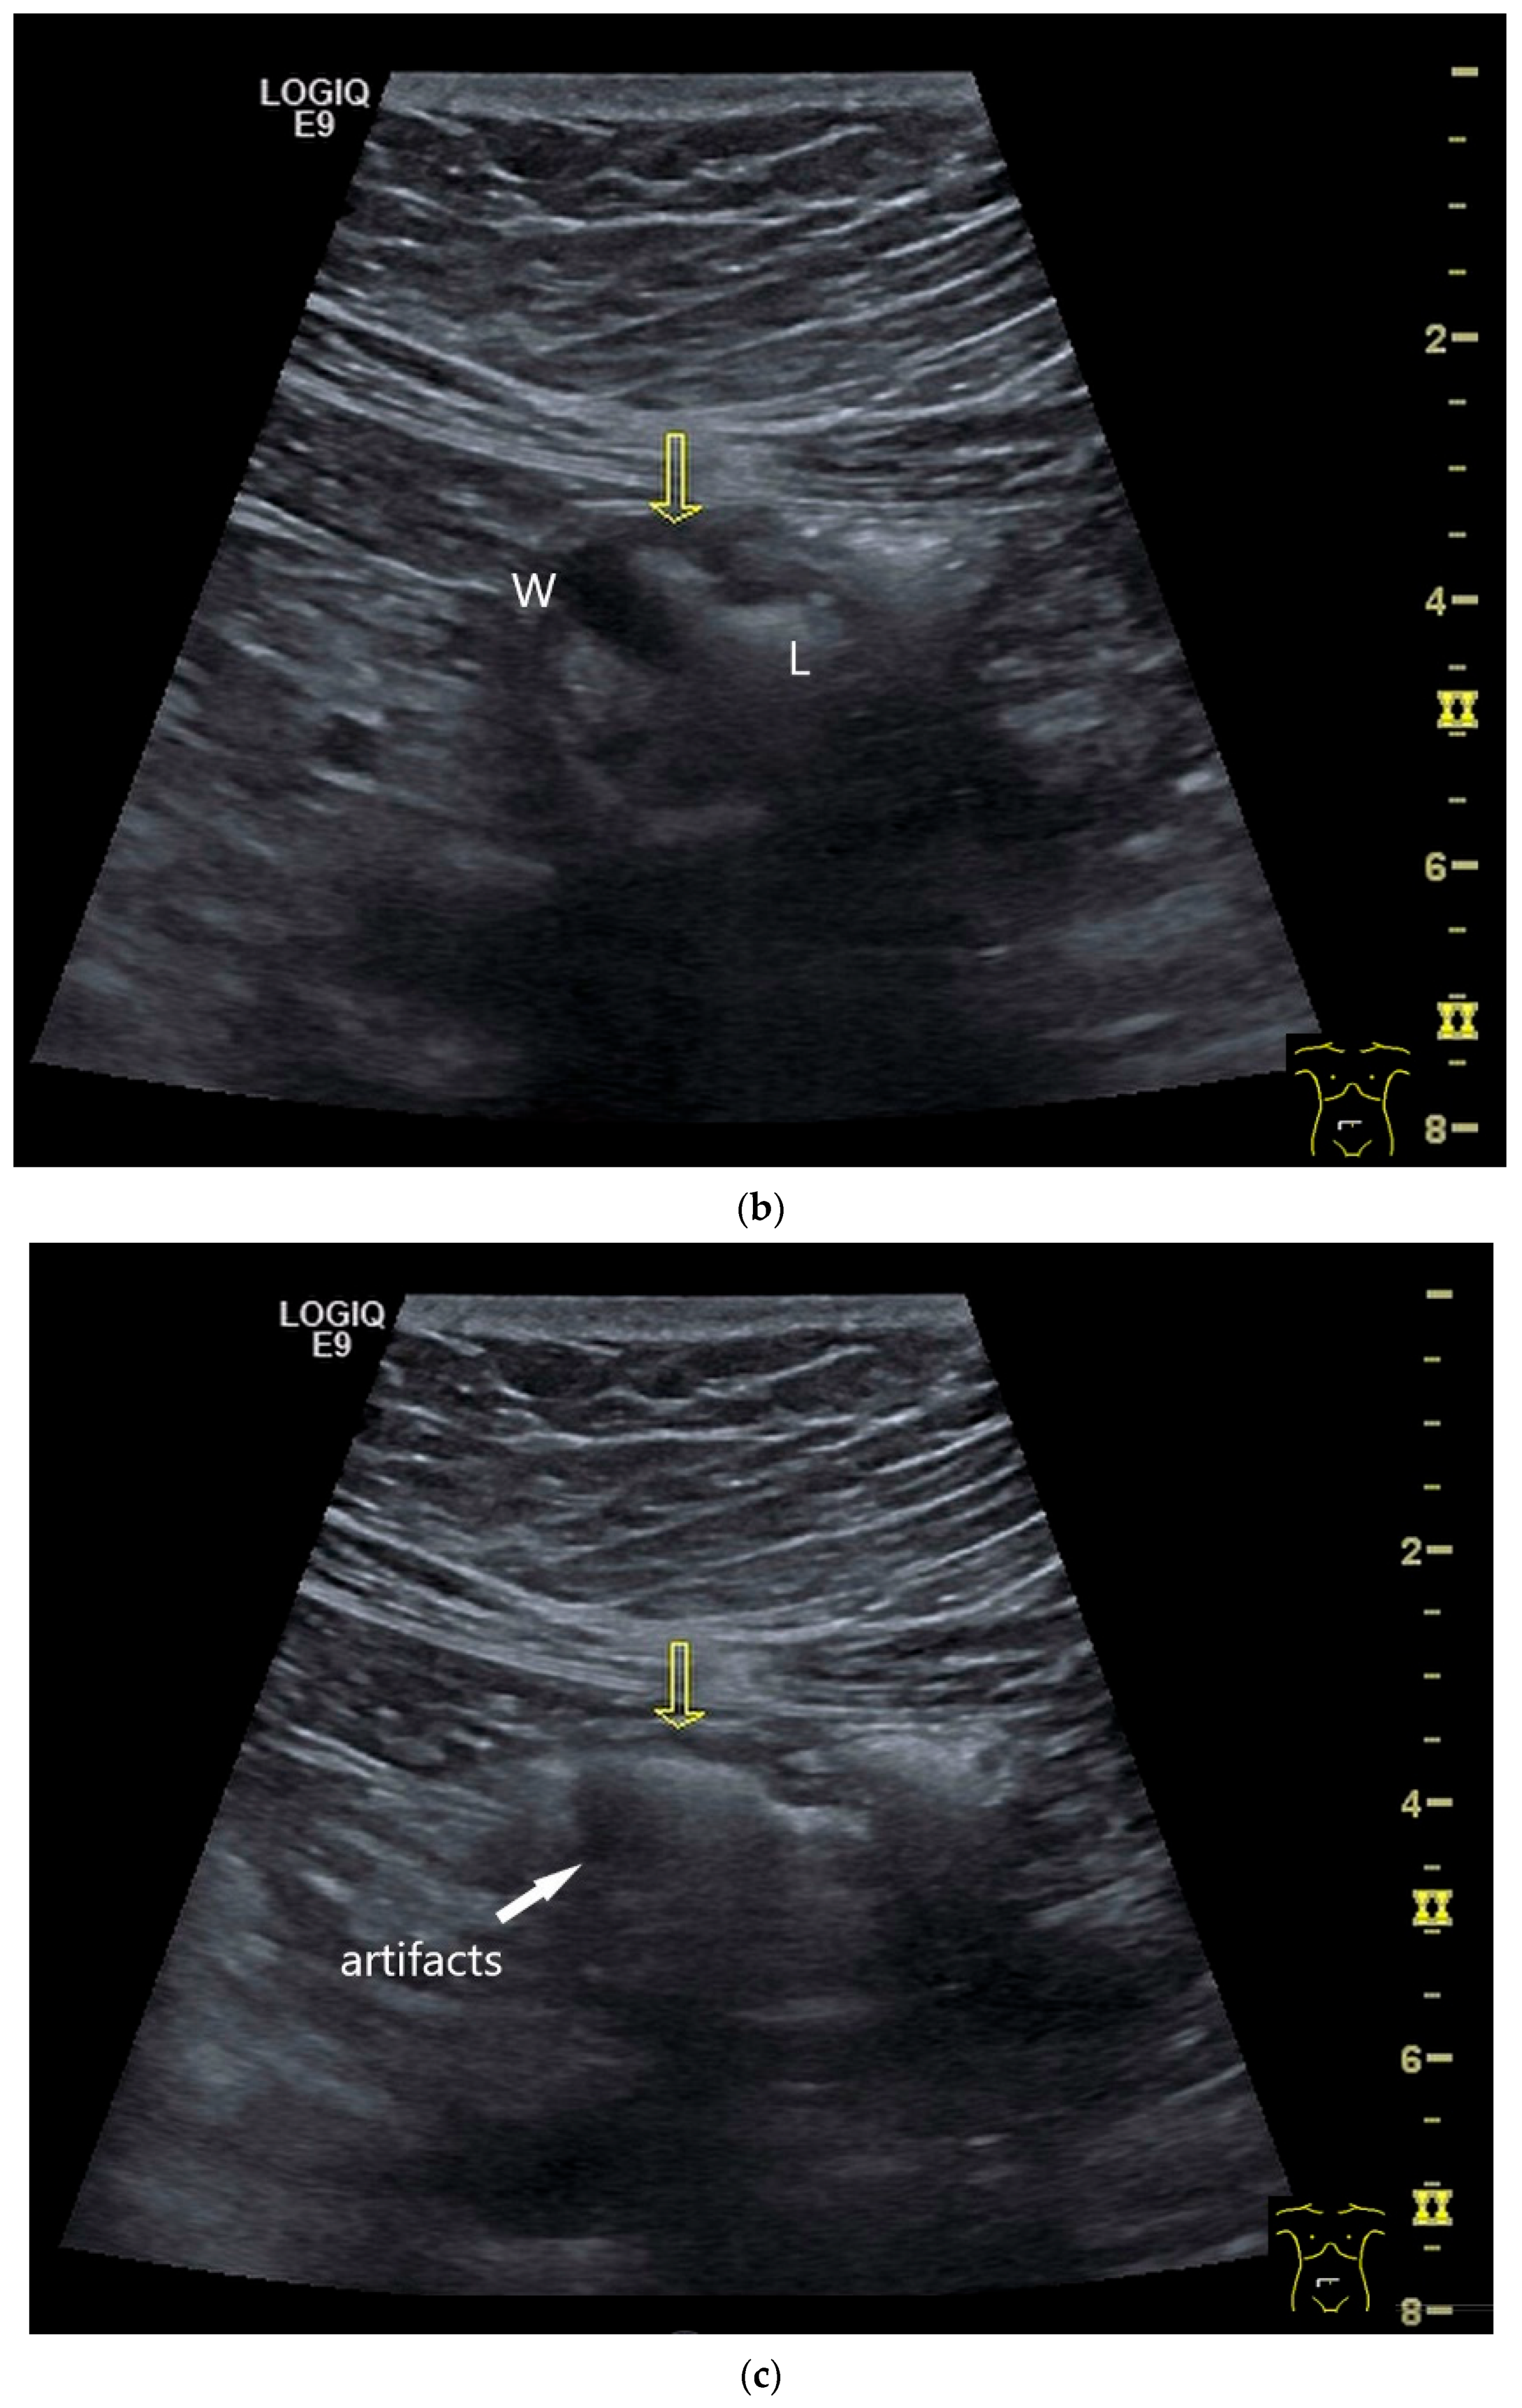

- Smereczyński, A.; Starzyńska, T.; Kołaczyk, K. Mesenteric changes in an ultrasound examination can facilitate the diagnosis of neuroendocrine tumors of the small intestine. J. Ultrason. 2015, 15, 274–282. [Google Scholar] [CrossRef]

| Neuroendocrine tumor | Small, nodular hypoechoic wall thickenings, mostly in the submucosa with spreading into the other layers. Usually with small vessels on CDI. Regionally enlarged lymph nodes. Multilocular manifestations are possible. |